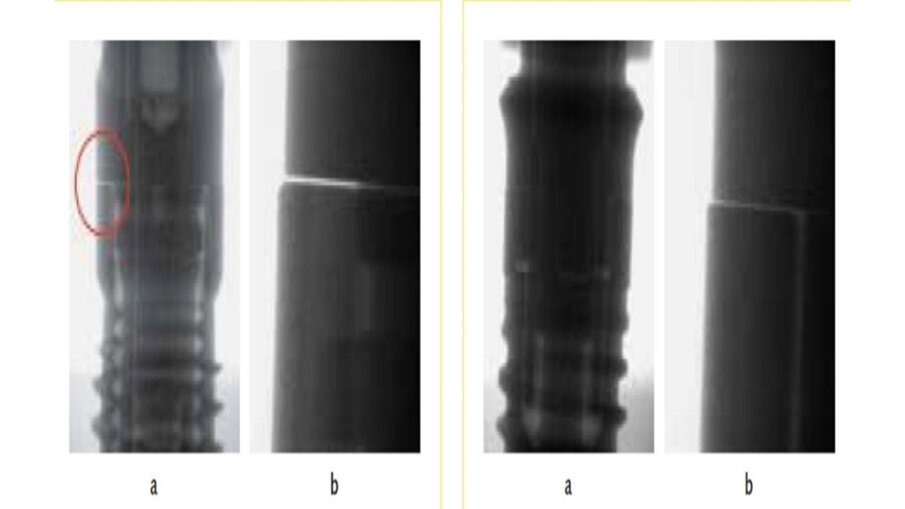

Obr. 4a–d: Detailní snímky dvou spojení implantátu a abutmentu při zatížení žvýkacím tlakem.

Procesem zavádění může dojít k narušení původního povrchu implantátu a jeho tvaru. Velmi hluboké zavádění způsobuje větší poškození kosti a implantátu než zavádění za menší síly. Vlivem torze a frikce implantátu v kosti se z povrchové struktury implantátu uvolňují do již tak poškozené kostní tkáně částice titanu. Velikost uvolňujících se částic titanu se pohybuje v rozmezí 10 až 20 μm. Na ostrých hranách implantátu dochází v důsledku zavádění k částečné ztrátě celé oxidové vrstvy. Ztráta oxidové vrstvy také závisí na typu implantátu. Martini a kol. dokázal, že implantáty potažené fluorohydroxyapatitem byly méně náchylné k abrazi během zavádění než implantáty potažené plazmou. Částice titanu uvolněné z implantátů potažených plazmou se nacházely ve vzdálenosti 200–250 μm od povrchu implantátu a zabraňovaly neo-osteogenezi. Deformaci závitu implantátu lze pozorovat v oblasti kosti, konkrétně v podobě mikrotrhlin. Abradované částice titanu se nachází jak ve sliznici kolem implantátu, tak i v nově vytvořené kosti. Částice titanu však byly zjištěny dokonce i ve vzdálenějších orgánech: v játrech, ledvinách, plicích a srdci. Dalším faktorem, který přispívá k uvolňování kovových částic, je kromě zavádění implantátu i vysoké mechanické zatížení na spojení mezi implantátem a abutmentem. Důsledkem může být také úplné selhání implantátu. Navíc se mohou na spojení implantátu a abutmentu vytvořit mikroskopické mezery, jimiž se také mohou uvolňovat částice titanu a kovu obecně. Dalšími možnými následky mikroskopických mezer mohou být mikro netěsnosti, opotřebení materiálu, únava ateriálu a uvolnění šroubků. Mikro netěsnosti jsou zvlášť patrné u šestihranných volnějších spojení (obr. 4a–d) a skrz ně – kromě abraze kovu a poškození materiálu – získávají tekutiny a bakterie přístup do vnitřku implantátu a způsobují vnitřní korozi implantátu. Pohyby mikroskopických mezer je možné zredukovat kónickým spojením mezi implantátem a abutmentem.